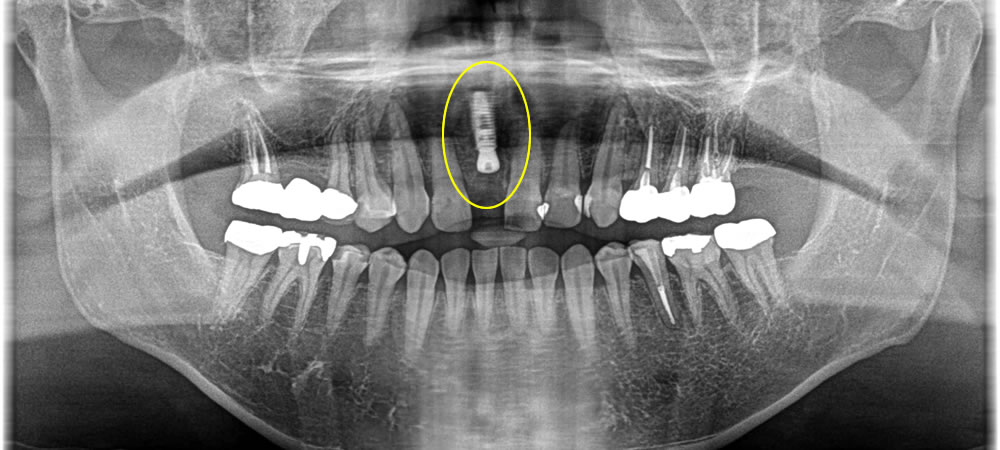

抜歯~インプラント埋入手術の実施

骨欠損の範囲がかなり大きかったため、インプラント体の安定のため骨造成も同時に行いました。インプラントと骨が結合するまでの期間は、歯が無いと前歯なので見た目が悪いとの事で、治療用義歯(ノンクラスプ)を作成し、見た目の改善を行いました。また、待機期間中にホワイトニングも行い、より審美的にこだわって上部構造を作製しました。